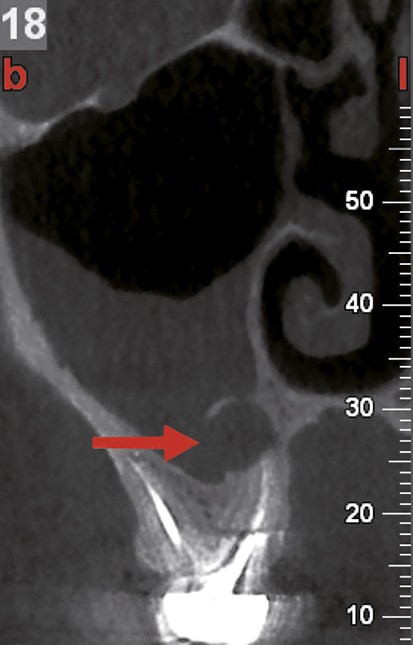

Si les isthmes sont particulièrement mis en évidence au niveau des molaires mandibulaires, cela devient médicalement important au niveau des molaires maxillaires.

La diffusion bactérienne et de leurs toxines, au niveau des molaires maxillaires est à l’origine d’un grand nombre de sinusites maxillaires chroniques, d’origine dentaire. Celles-ci sont principalement causées par l’absence de traitement du deuxième canal MV, qui existe dans 90 % des cas, et il est à noter que ces deux canaux – MV1 et MV2 – sont également reliés par un isthme.

Le nettoyage des isthmes intercanalaires reste un réel problème, et semble responsable de nombreux échecs [43]. Par ailleurs, il est nécessaire d’utiliser des instruments qui évitent de propulser les débris, tant apicalement que latéralement, en obturant les entrées isthmiques avec des débris compactés.

Le passage du laser est répété plusieurs fois, en début, au milieu et en fin de préparation. Un protocole peut alors être proposé : 40 mJ ; 20 Hz (fig. 7). L’utilisation de biocéramiques Bioroot (Septodont) ou Total Fill R (FKG) permet de sceller le système ainsi nettoyé, en assurant une action biologique de longue durée [46] (fig. 8a à c).